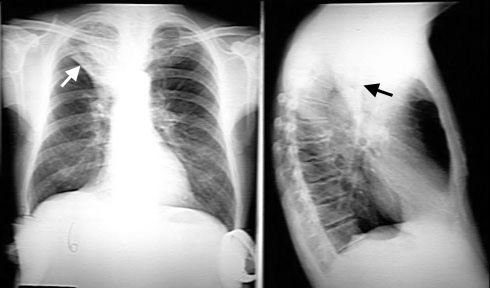

RUL atelectasis

• Density in projection of the right upper lung field.

• Triangular in shape with narrow end towards the hilum (lobar configuration).

• Transverse fissure has moved up (white arrow).

• Right hilum has moved up.

• In the lateral view, the transverse fissure has moved up towards the oblique fissure (Black arrow).

• All signs of RUL lung volume loss.

This is resorptive atelectasis due to bronchial obstruction (cancer lung).